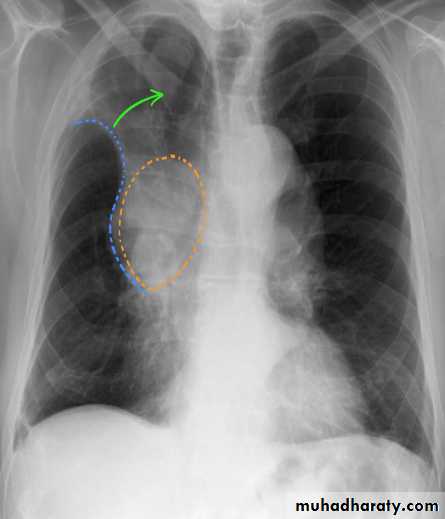

Right upper lobe collapse has distinctive features, and is usually easily identified on frontal chest radiographs .

Radiographic features

Chest radiograph

Collapse of the right upper lobe is usually relatively easy to identify on frontal radiographs. Features consist of :

increased density in the upper medial aspect of the right hemithorax

elevation of the horizontal fissure

loss of the normal right medial cardiomediastinal contour

elevation of the right hilum

hyperinflation of the right middle and lower lobe result in increased translucency of the mid and lower parts of the right lung

right juxtaphrenic peak

A common cause of lobar collapse is a hilar mass. When a right hilar mass is combined with collapse of the right upper lobe, the result is an S shape to elevated horizontal fissure. This is known as Golden S sign .

Non-specific signs indicating right sided atelectasis are also usually present including:

elevation of the hemidiaphragm

crowding of the right sided ribs

shift of the mediastinum and trachea to the right